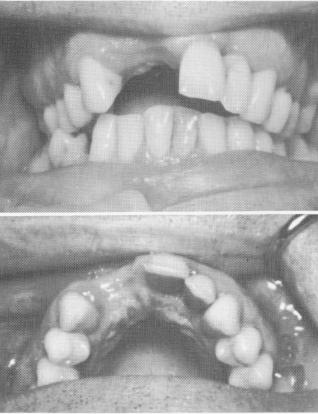

Fig. 12-85. A, A preoperative picture showing missing right central and lateral incisors. B, There were no caries or preexisting fillings in any of the teeth.

PARTIAL MAXILLARY SUBPERIOSTEAL IMPLANTS WITH HORIZONTAL TRANSFIXATIONS

Horizontal pins may be used to help stabilize and support a maxillary subperiosteal implant. In this case, a 32-year-old man was missing right maxillary central and lateral teeth (Fig. 12-85) . He had neither decay nor fillings in any of his maxillary teeth. His anterior quadrant flared out anteriorly so that there was an overjet of about 5 or 6 mm. over the lower teeth. In order to spare the neighboring teeth from full crown restorations, a unilateral subperiosteal im-